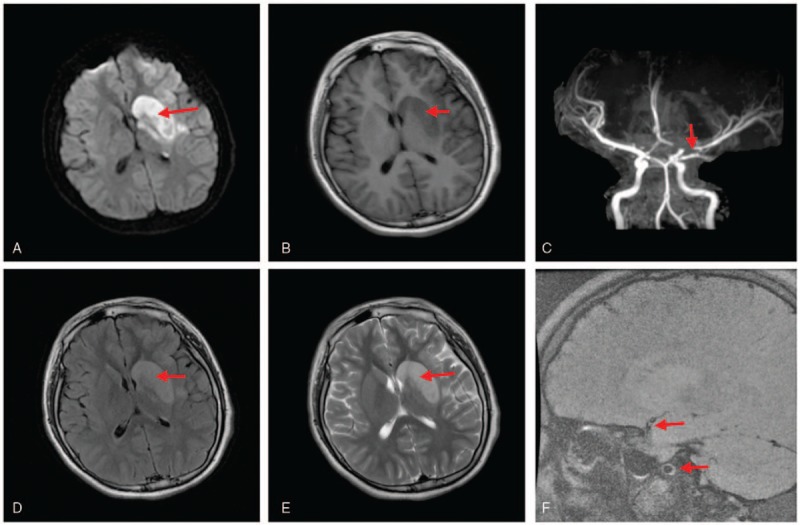

A 14-year-old male patient exhibited a sudden speechlessness and weakness in the right limb weakness for 8 hours. Subsequently, he became unconsciousness with a transient twitch in the right limb. After a few seconds, the convulsions disappeared, and consciousness was regained. The patient was checked in a local hospital and brain computed tomography (CT) did not show any abnormalities. For further treatment, the patient was admitted to our hospital. The patient had no headache, dizziness, fever, and diarrhea before the illness and no strenuous exercise was performed. Also, the patient had a history of “bronchial asthma” and “allergic rhinitis” for 11 years. The patient's mother has a history of “hypertension and diabetes.” Physical examination found that the patient had a clear consciousness but also motor aphasia. Both eyes were gazing towards the left side, the right side of the nasolabial sulcus was shallow, and the tongue was biased towards the right side while stretching. The tension of the left limb muscle was normal, and the left limb muscle strength was grade 5. The muscle tension on the right side is slightly lower, and the muscle strength level of the right upper limb is grade 0 and the muscle strength of the right lower limb grade 2. The pathological sign of the left side was (−) and that of the right side was (+). National Institutes of Health Stroke Scale (NIHSS) score was 14 points. Auxiliary examination: erythrocyte sedimentation rate (ESR): 9 mm/h (0–15); blood biochemistry: uric acid 503 μmol/L (208–428); creatine kinase: 566 IU/L (50–310); lactate dehydrogenase: 251 IU/L (120–250); low-density lipoprotein cholesterol: 3.24 mmol/L (1.53–3.45); HDL cholesterol: 0.94 mmol/L (1.04–1.96); C-reactive protein (CRP): 4.29 mg/L (0–8). The results of blood routine test, 4 coagulation tests, urine routine test, stool routine test, glycosylated hemoglobin, pre-transfusion test, autoantibody test, humoral immune series, anti-neutrophil cytoplasmic antibody and subtype, anticardiolipin antibodies, and blood lactic acid were normal. Brain magnetic resonance imaging (MRI) and magnetic resonance angiogram (MRA) (Fig. 1) showed multiple flake-shaped shadow of longer T1 and T2 signals in the left basal ganglia and frontal-parietal lobes. Fluid-attenuated inversion recovery (FLAIR) and diffusion-weighted imaging (DWI) images showed high signals. The local sulcus disappeared with slight mass effect. Color ultrasound of liver, gallbladder pancreas, spleen, and kidney displayed a fatty liver at 2 cm under the liver ribs. The results of electrocardiogram, color ultrasound of heart, cervical vessels, lower extremity veins, and brain CT were normal. The digital subtraction cerebral angiography (Fig. 2) showed stenosis of C6 and C7 segments on the left internal carotid artery, with stenosis rate of about 60% to 70% and 80%, respectively. During the course of hospitalization, the patient presented with acute onset of speechlessness accompanied by the weakness in the right limb weakness. Physical examination revealed aphasia and central paralysis in the right limb. MRI examination showed new cerebral infarction lesions on the left basal ganglia and frontal lobe. MRA presented intracranial vascular multiple stenosis located on the left frontal-parietal cortex, the left cortical nucleus, corticospinal tract, the left basal ganglia, caudate nucleus, lentiform nucleus, and the left middle cerebral artery (MCA)-dominated area. High-resolution brain MRA (Fig. 1), conducted during hospitalization of the patient, showed atherosclerotic plaques on the left atrial carotid artery and the MCA. Digital subtraction angiography (DSA) showed severe stenosis at the end of the left internal carotid artery and proximal occlusion on the left anterior cerebral artery and the MCA. The patient was diagnosed as ischemic stroke. Lower HDL-C (0.506–0.94) and atherosclerotic stenosis of the patient were detected by comprehensive serological examination and vascular examination, respectively. Furthermore, the serum lipid metabolism-related gene examinations showed exon22 in ABCA1 gene; c.598G>A, p.1068R>H, and 899–1131 amino acids position harbored the domain of ABCA1 transporter. Simultaneously, the evaluation of his parents’ genes revealed a heterozygous mutation of the Tangier disease-related ABCA1 gene in the sample of the patient, which was proved by family verification results (Fig. 3) that were from the mother. Based on the above results, we diagnosed the patient with a genetic Tangier disease. After exclusion of mitochondrial encephalomyopathy, intracranial infection, arterial stroke, sickle cell disease, and other diseases, the cause of cerebral infarction was clarified. The hereditary metabolic abnormalities were assessed qualitatively. Then, we conducted a family survey of the disease that revealed only the patient with this disease in the 3 generations of his family (Fig. 4). The mother was a healthy gene carrier, and the father did not have a gene mutation. The thorough serological examinations of the immediate family members of the parents showed normal HDL. Although gene detection was not complete, the mother was found to be normal without any cerebral infarction. The patient was administered anti-platelet aggregation and statin, and other comprehensive treatments. Simultaneously, the patient underwent body weight control, ingested diet with low salt and low fat, and physical rehabilitation training. After treatment for 24 days, the patient showed improvement and was discharged. Before discharge, biochemical reexaminations revealed lactate dehydrogenase 243 IU/L, HDL cholesterol 1.04 mmol/L, low-density lipoprotein cholesterol 2.29 mmol/L. Physical examination revealed incomplete motor aphasia and the right upper limb muscle strength was level 0, and the right lower limb muscle strength was level 2+. Three months after discharge, the results of reexaminations showed 0.506 mmol/L HDL.

Figure 1.

(A, B, D, E) Multiple flake-shaped shadow of longer T1 and T2 signals in the left basal ganglia and frontal-parietal lobes. FLAIR and DWI images showed high signals. (C, F) Multiple segmental severe stenosis at initial segment of the left anterior cerebral artery and M1 proximal segment of the MCA; the initial segment of the right anterior cerebral artery was slightly thinner (red arrow). DWI = diffusion-weighted imaging, FLARE = fluid-attenuated inversion recovery, MCA = middle cerebral artery.